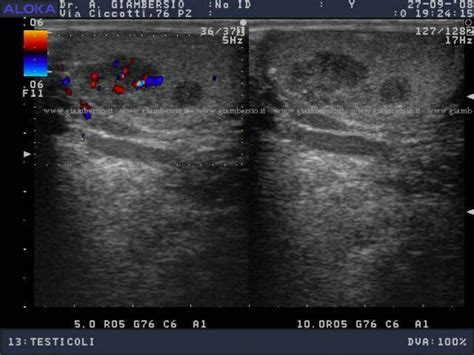

- Ecografia Scrotale: Questa indagine non invasiva utilizza ultrasuoni per visualizzare l'interno dello scroto, fornendo dettagli sulla posizione, le dimensioni e la natura (solida o liquida) di eventuali anomalie.